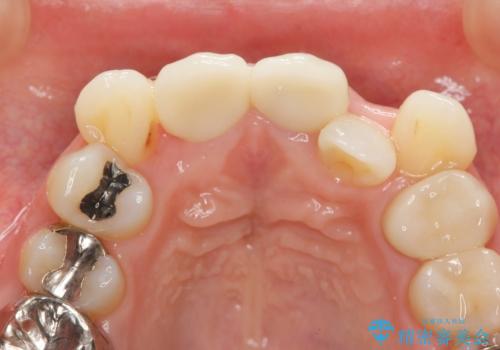

子供の頃にぶつけた前歯 根管治療から行うセラミック治療

- 幼少時にぶつけ、神経を取った歯の審美改善を求めて来院されました。

X線写真より不十分な根管治療、根尖病変、前歯の変色が認められます。

歯根の近接のみられる右上側切歯を抜去し、根管治療を伴うセラミック治療を計画します。